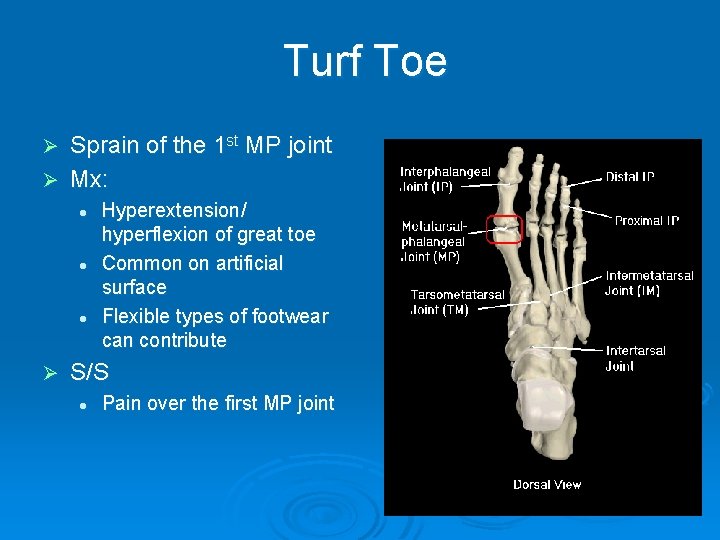

Turf Toe Sprain of the 1 st MP joint Ø Mx: Ø l l l Ø Hyperextension/ hyperflexion of great toe Common on artificial surface Flexible types of footwear can contribute S/S l Pain over the first MP joint